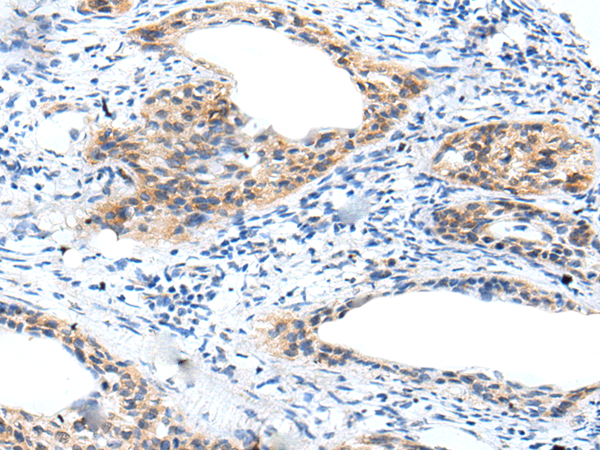

ELISA, IHC |

IHC positive control: |

Human cervical cancer |

IHC Recommend dilution: |

10-50 |